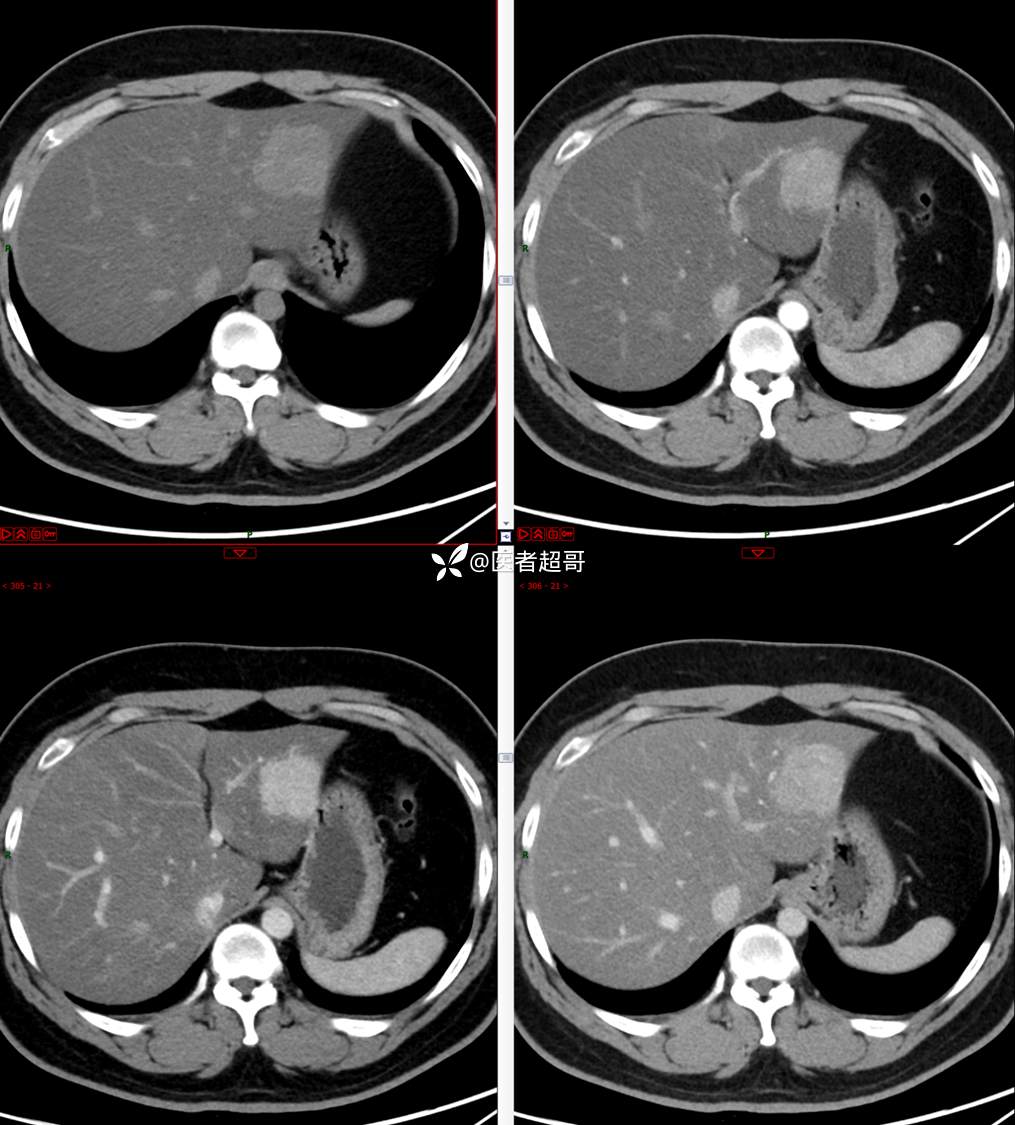

【影诊笔记685】男,31y,发现肝占位性病变5天就诊,请诊断分析,有病理结果!

主 诉:发现肝占位性病变5天。

现病史:患者缘于5天前体检时发现肝占位性病变,未予以特殊处置。现患者为求系统诊治就诊于我院,行普美显提示:肝左叶富血供占位,请结合临床及其他检查,肝多发血管瘤,脂肪肝,肝囊肿,请结合临床。门诊以“肝占位性病变”收入我科。病程中,饮食睡眠可,二便可,近期体重未见明显变化。